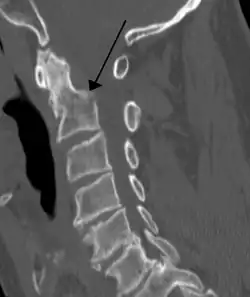

Fractures

Fractures of the dens are classified into three categories according to the Anderson Alonso system:

• Type I fracture - Extends through the tip of the dens. This type is usually stable.

• Type II fracture - Extends through the base of the dens. It is the most commonly encountered fracture for this region of the axis. This type is unstable and has a high rate of non-union.

• Type III fracture - Extends through the vertebral body of the axis. This type can be stable or unstable and may require surgery.[1]